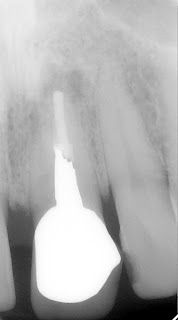

| before my treatment: note gray area (inflamation) around the tip of the root already treated somewhere, but failure with swelling and pain |

| 10 years after my treatment: note shrinkage of inflamation around the root tip no symptoms since the treatment |